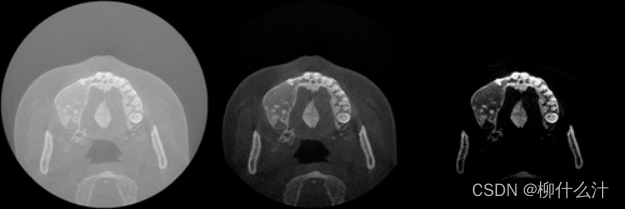

窗口/水平的影响。左图:大宽度的窗口覆盖整个图像的灰度值范围,导致图像对比度差。中间:中等宽度的窗口覆盖软组织和骨骼的灰度值,导致良好的整体对比度。右图:小宽度的窗口有一个高级值,导致骨和牙齿的高对比度。